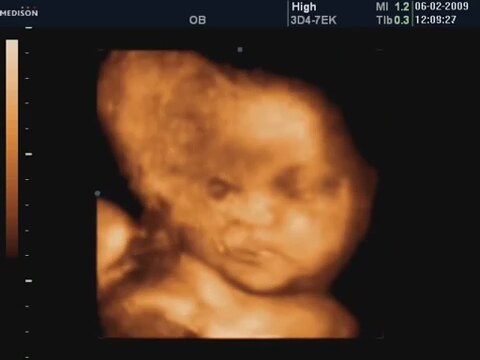

33 Haftalık Bebeğin 4 Boyutlu Ultrason Görüntüsü